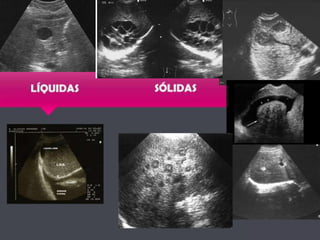

De qué nosacordamos…???  ANECOICAS  HIPOECOICAS  ISOECOICAS  HIPERECOICAS  Artefactos